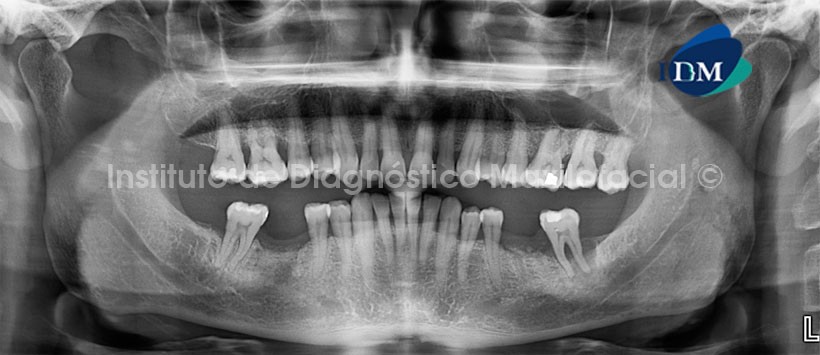

La CBCT es un estudio esencial en la visualización de este tipo de fracturas más aún si lo hacemos con alta resolución y con campos (FOV) pequeños. En último caso, todas las posibles fracturas deben ser estudiadas bajo exploración en dos planos perpendiculares entre sí que permitan valorar posibles desplazamientos.